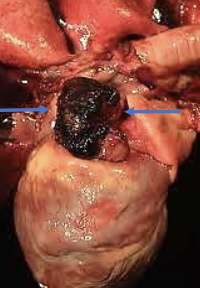

what are the common primary cardiac sites of hemangiosarcoma?

second most common primary site:

-right atrium

-right auricle